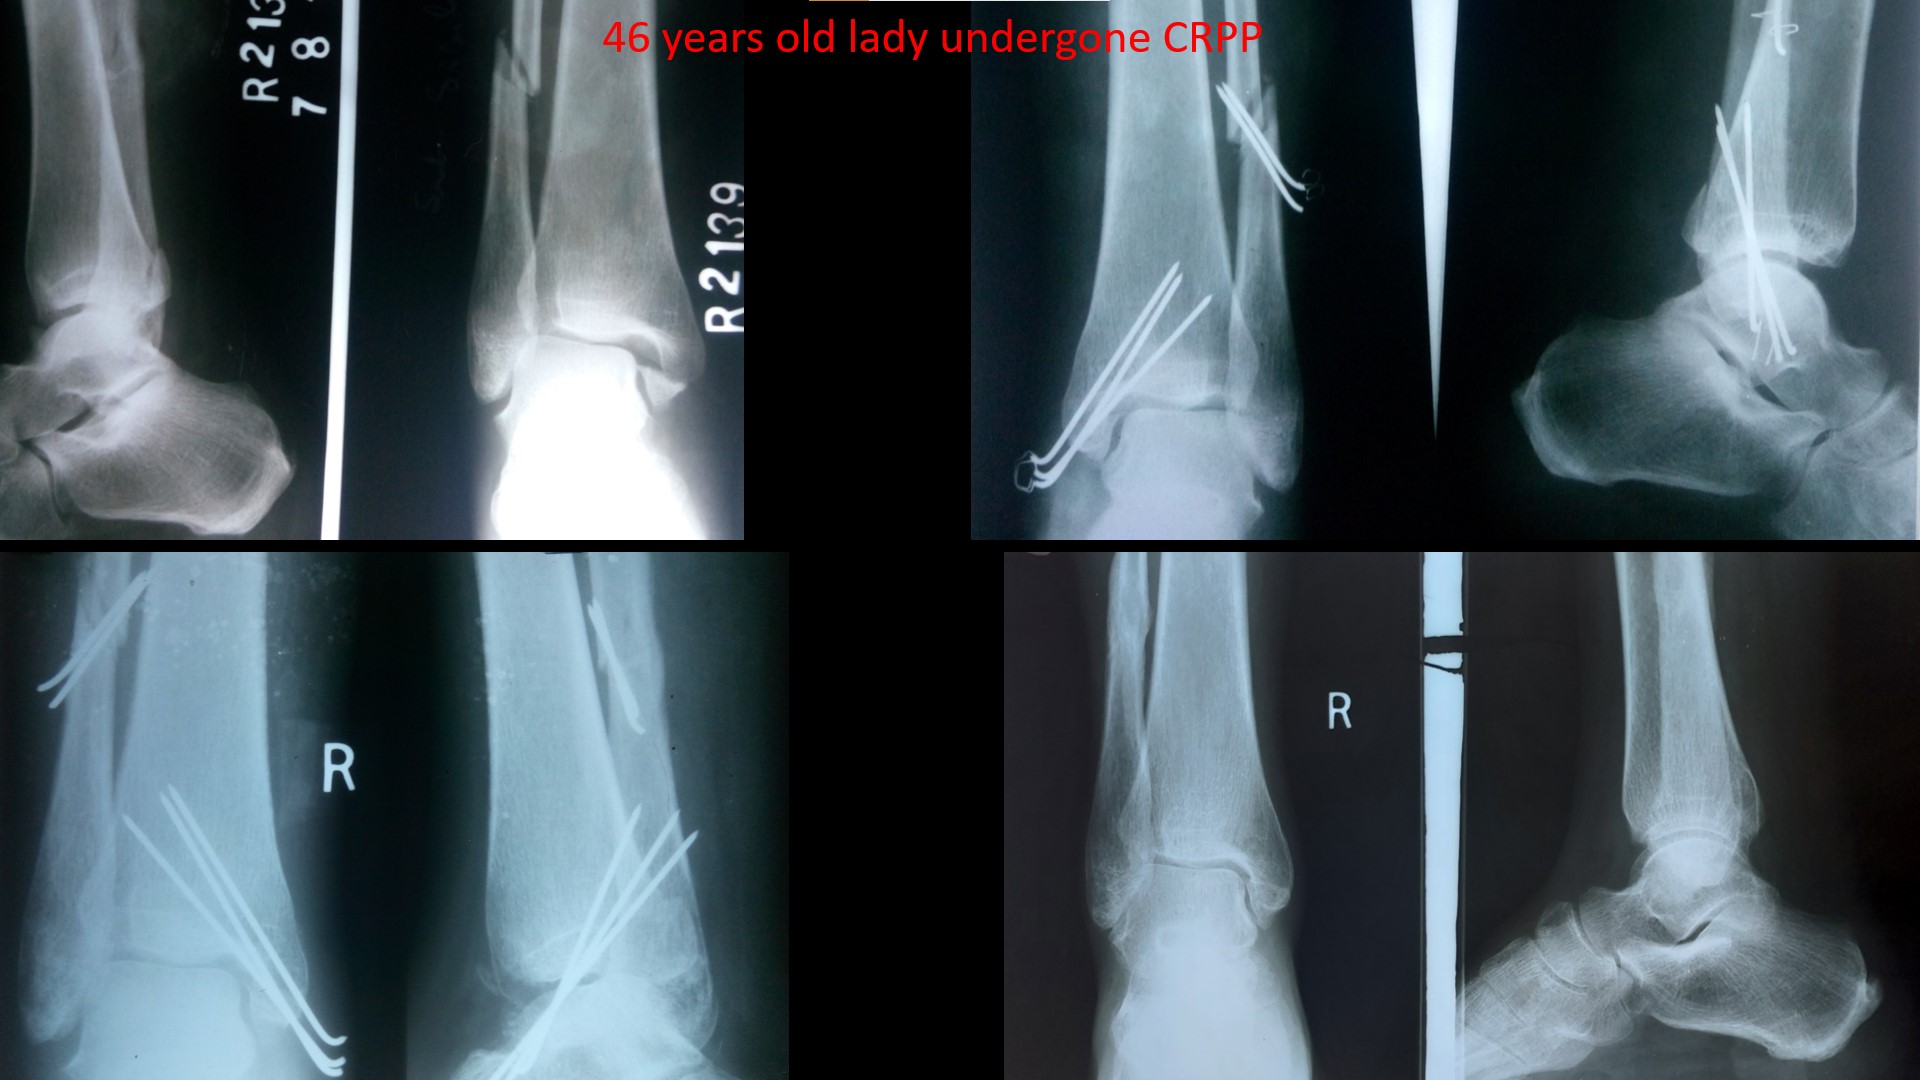

ANKLE